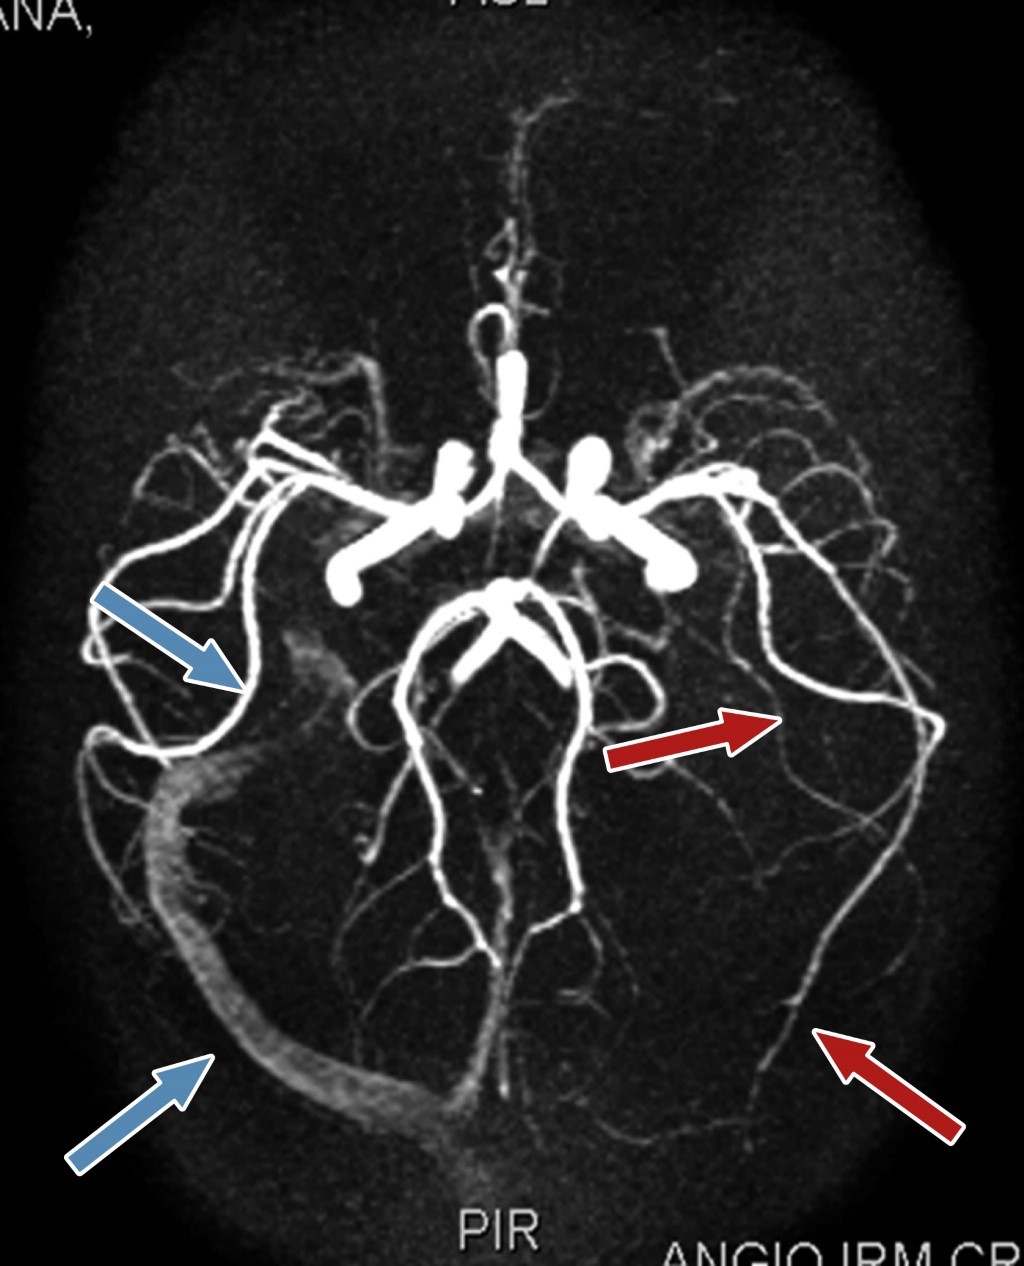

Al examen físico se evidenció otalgia izquierda asociada a dolor y aumento en la sensibilidad en la región mastoidea. Los exámenes solicitados revelaron leucocitosis (18.770/mm3) con neutrofilia, trombocitosis (628.000/mm3), elevación de reactante de fase aguda PCR 8.35 mg/dL (valores normales 0.10-0.30 mg/dL), elevación de ferritina 250.20 ng/dL (valores normales 7-140 ng/dL). Ante la alta sospecha de otomastoiditis, se inició terapia antibiótica intravenosa con ceftriaxona (100 mg/kg/día) y vancomicina (60 mg/kg/día). La paciente fue valorada por los servicios de neurología, neurocirugía e infectología; se solicitó estudio de imágenes y se realizó tomografía contrastada del cerebro, donde se evidenció una imagen hipodensa en el hemisferio izquierdo, compatible con absceso cerebral, además de signos de trombosis del seno sigmoideo izquierdo. En el corte de hueso mastoideo izquierdo se evidenciaron signos de hiperdensidad, confirmándose la otomastoiditis (Figura 1). Debido a ello, se solicitó resonancia magnética de cerebro (Figura 2), así como venografía cerebral (Figura 3), evidenciándose el absceso en el lóbulo temporal izquierdo, rodeado por edema perilesional y ausencia de flujo sanguíneo en el seno venoso transverso y sigmoideo izquierdo.

Figura 3